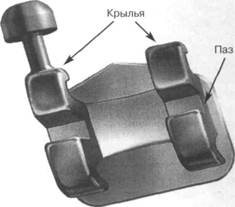

Эджуайз-техника возникла благодаря созданию оригинальных по конструкции замковых приспособлений — брекетов и основных силовых элементов техники — прямоугольных, круглых или квадратных в сечении проволочных дуг. В переводе с английского термин «edgewise» означает «край в край», т.е. проволочная ортодонтическая дуга фиксируется в замковое приспособление — брекет, имеющее плоскую прорезь. Эджуайз-техника (бре-кет-система) является сложным по конструкции и высокоэффективным механизмом современной ортодонтической механотерапии, которая позволяет создать функционально-эстетический оптимум в зубо-челюстной системе (рис. 13.48). В элементную базу эджуайз-техники входят замковые приспособления — брекеты, щечные и небные трубки, проволочные ортодонтические дуги круглого, квадратного и прямоугольного сечения, дополнительные элементы в виде пружин, эластичных колец и цепочек. Замковые приспособления — брекеты — фиксируются на коронке зуба с вестибулярной поверхности и максимально передают силовое действие прово-

Рис. 13.49. Конструкция брекета.

Конструкция брекета эджуайз-техники состоит из следующих элементов (рис. 13.49):

• паза, располагаемого на лицевой поверхности замкового приспособления;

• крыльев, за счет которых проводится фиксация проволочных ор-тодонтических дуг с помощью проволочной или эластичной лигатуры;

• опорной площадки, посредством которой брекет фиксируется на клинической коронке зуба.